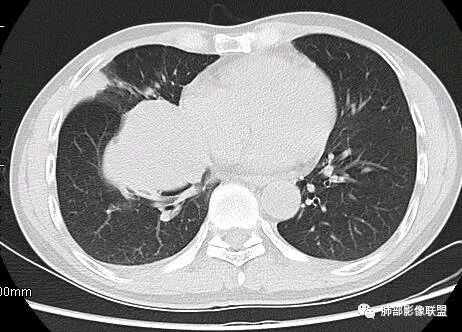

南边:结果:肉瘤

1.发生于肺组织的间叶源性恶性肿瘤相对少见,文献也常常以个案形式予以报道。包括滑膜肉瘤,纤维组织肉瘤,平滑肌肉瘤,多相分化的癌肉瘤,甚至极为罕见的横纹肌肉瘤等等。

2.相对于肺部的上皮源性恶性肿瘤(肺癌),肉瘤发病年龄偏轻,临床表现轻微,常常肿块较大时前来就医,或者体检意外发现。

3.肿块常常较大,甚至巨大,病灶边界一般清楚,影像上常有假包膜样结构、有膨胀性生长的特点,影像科医师有时甚至会纠结其来源于肺部或是胸壁纵隔。常见的肺癌肿块,很少有机会能长成这样的规模。

4.边缘可以有浅切迹,部分病灶会有铸型样外观,但大体十分圆钝,不会出现典型的分叶和毛刺,也很少会出现胸膜牵拉。支气管常推移,有明显的支气管阻塞时也较少观察到相关的阻塞性炎症。

5.病灶密度大多不均,不规则坏死液化,少数病例出现钙化。增强扫描常观察到由外而内的厚壁不均匀强化,中央半岛样强化等等,厚壁中或实性区常能显示血管影。一些病灶中央呈现边界清楚囊样变。